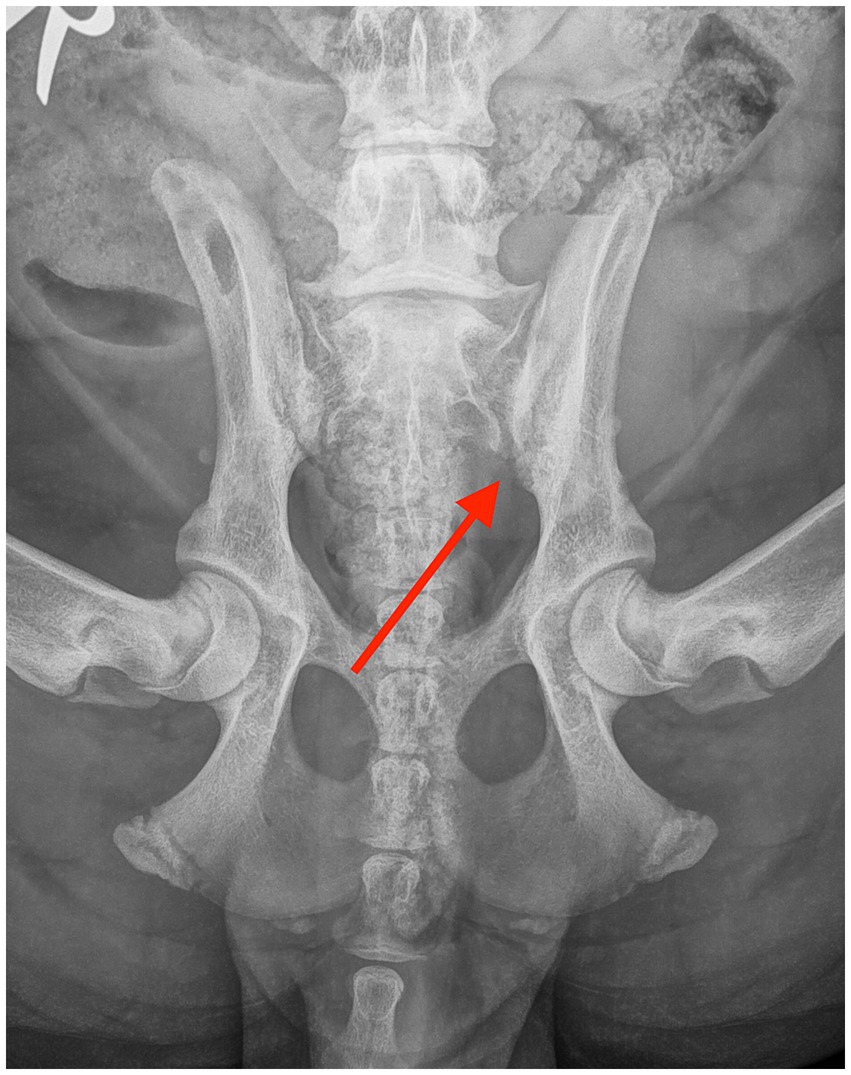

Figure 2. Ventrodorsal radiograph taken 6 weeks after the diagnosis, showing mild resolution of the erosive lesions in the sacroiliac joint (red arrow).

The patient was re-evaluated 3 weeks later. The dog was not lame and showed no pain on palpation of the lumbosacral or SIJ areas. Extension of the left hip was mildly restricted compared to the right hip. Metatarsal outward rotation was mild. Otherwise, the orthopedic examination was unremarkable. Physiotherapy was continued, and carprofen was administered at 2 mg/kg once daily for one more week. After a month, the dog was clinically normal. Metatarsal outward rotation was the same as before. The recheck radiographs after 6 weeks revealed a significant reduction in the size of the erosive changes, with an overall increase in bone opacity and reduced width of the SIJ spaces (Figure 2). The resolution of the radiographic changes was incomplete at this point.